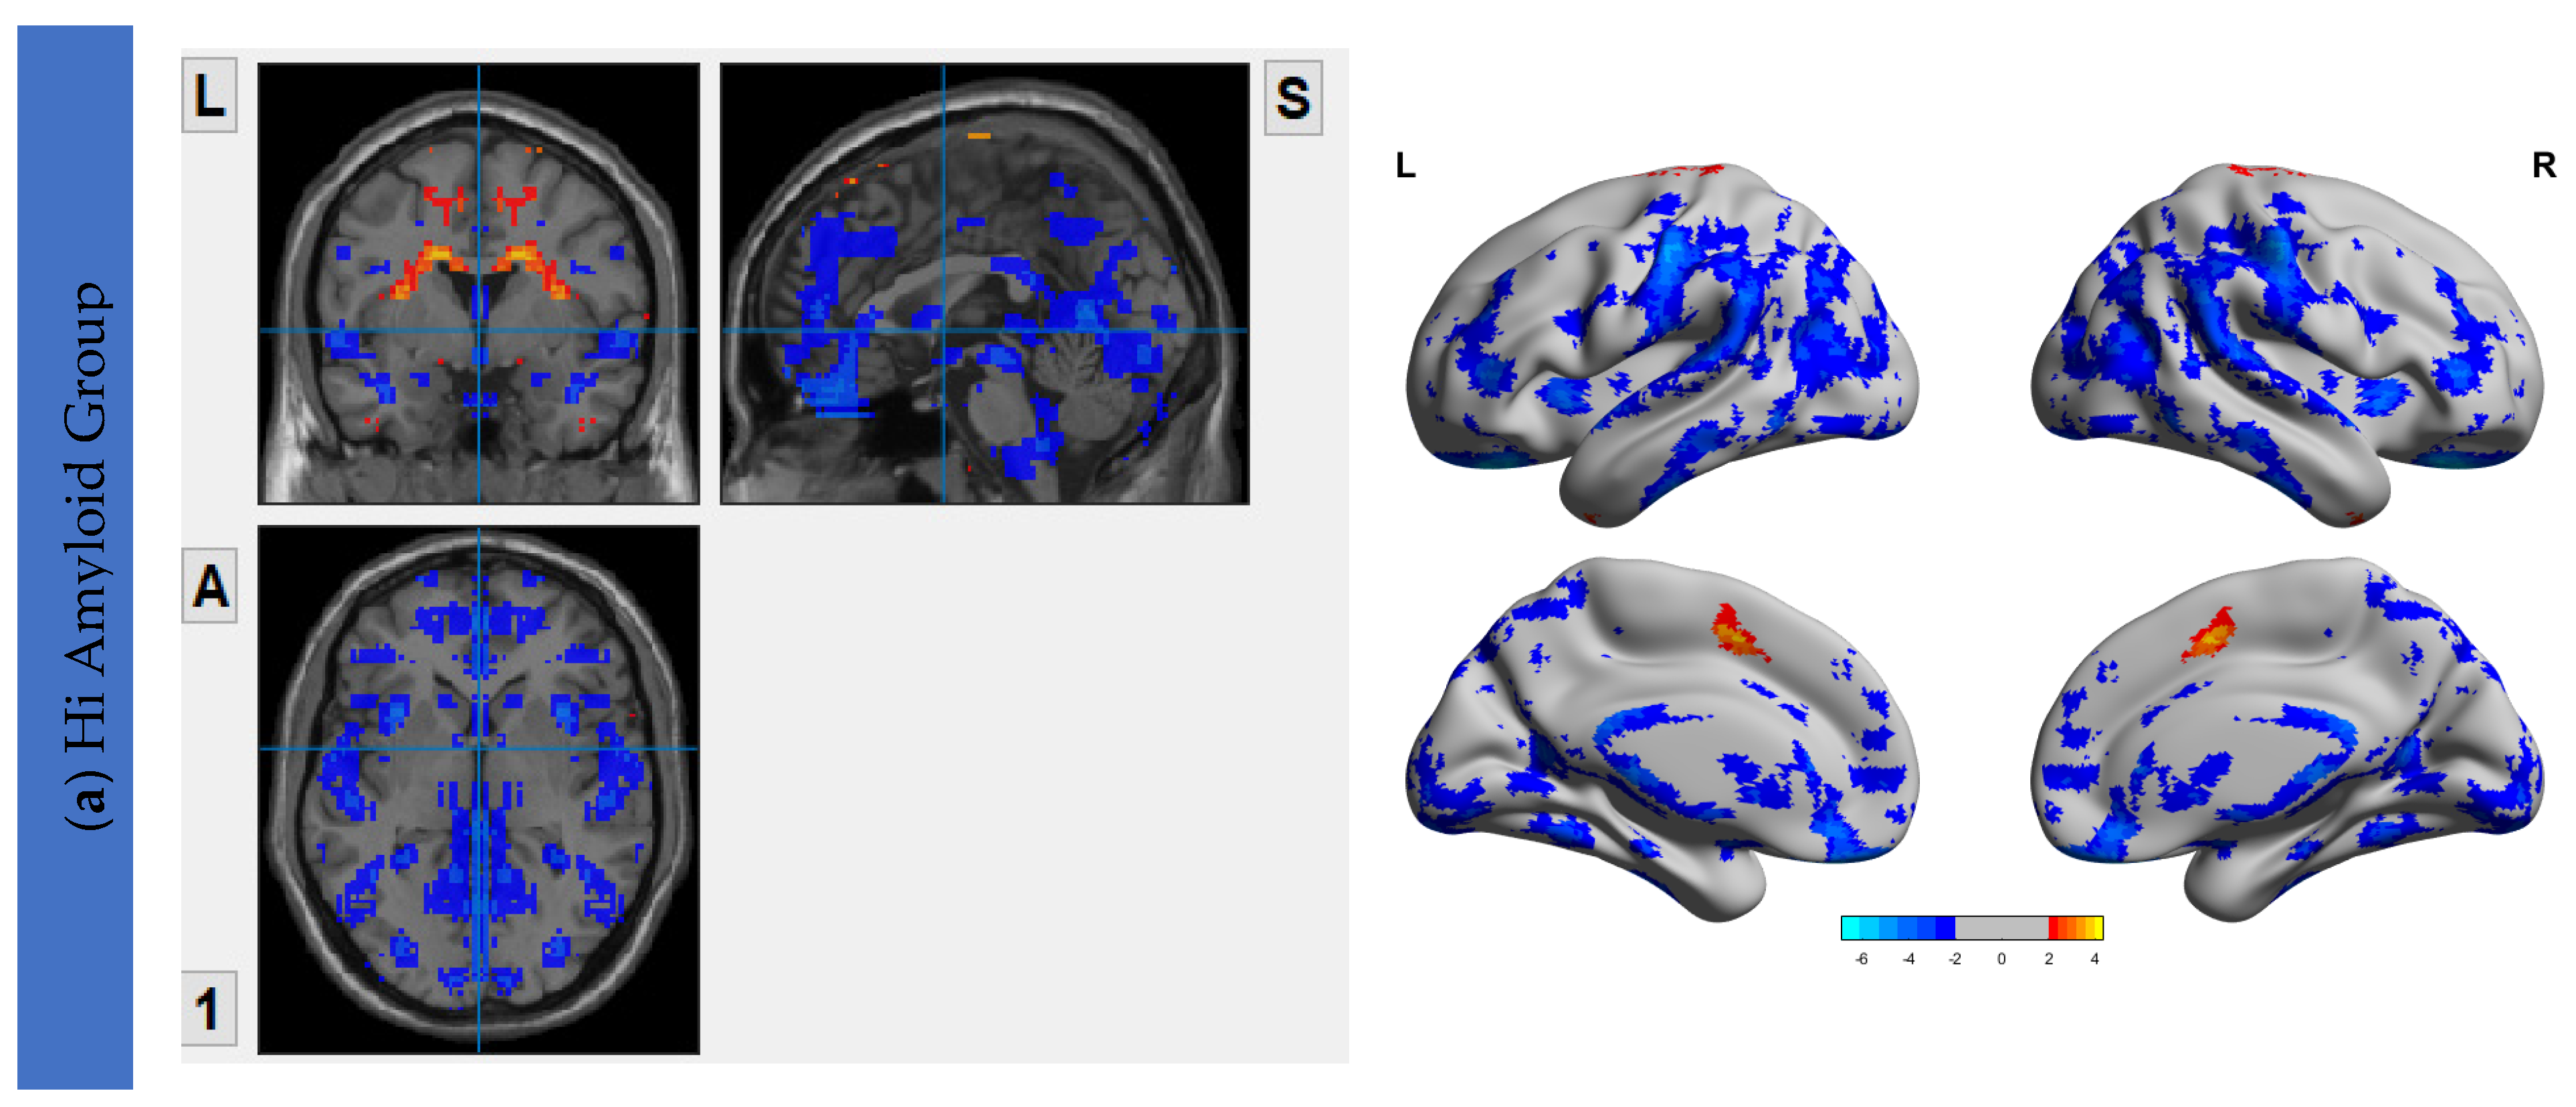

6.3. Interhemispheric Functional Connectivity (VMHC) Maps

7. Correlation Analysis between Aβ Accumulation and IFC

7.1. Within DMN

7.2. Within CEN

7.3. Within SN

7.4. Within SRN

7.5. Within SMN